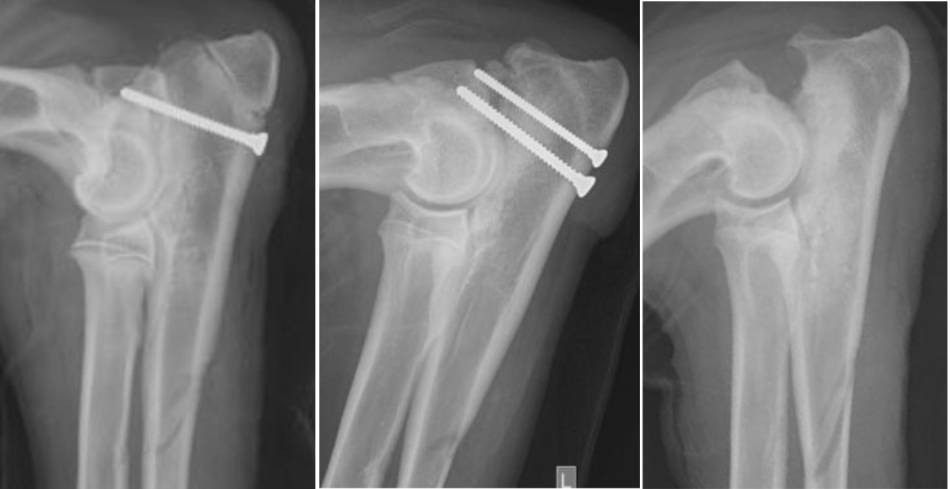

IPA Schraubenfixation

- Grad 1: Fissur, UPA nicht beweglich → gute Prognose nach OP: Zugschraubenfixation, distale / prox. Ulnaosteotomie

- Grad 2: UPA beweglich aber in situ → Zugschraubenfixation: variable Prognose bei frühzeitiger OP

- Grad 3: UPA stark beweglich und nicht mehr in situ, Erosion der Kontaktflächen, persistierende Inkongruenz → Exzission PA: vorsichtige bis gute Prognose